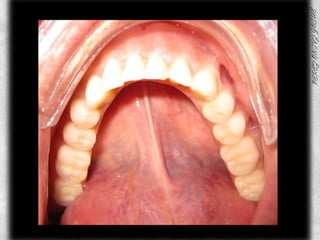

ARCADA SUPERIOR CLASIFICACIÓN DE OSAWA TIPO IFORMA DE PROCESO “U”LINEA MEDIA COINCIDE CON EL RAFE PALATINOCOLOR ROJO BRILLANTETEXTURA LISAPROCESO ALVEOLAR TIPO IAPARENTEMENTE SIN PRESENCIA DE CANDIDABUENA INSERCION DE LOS FRENILLOS